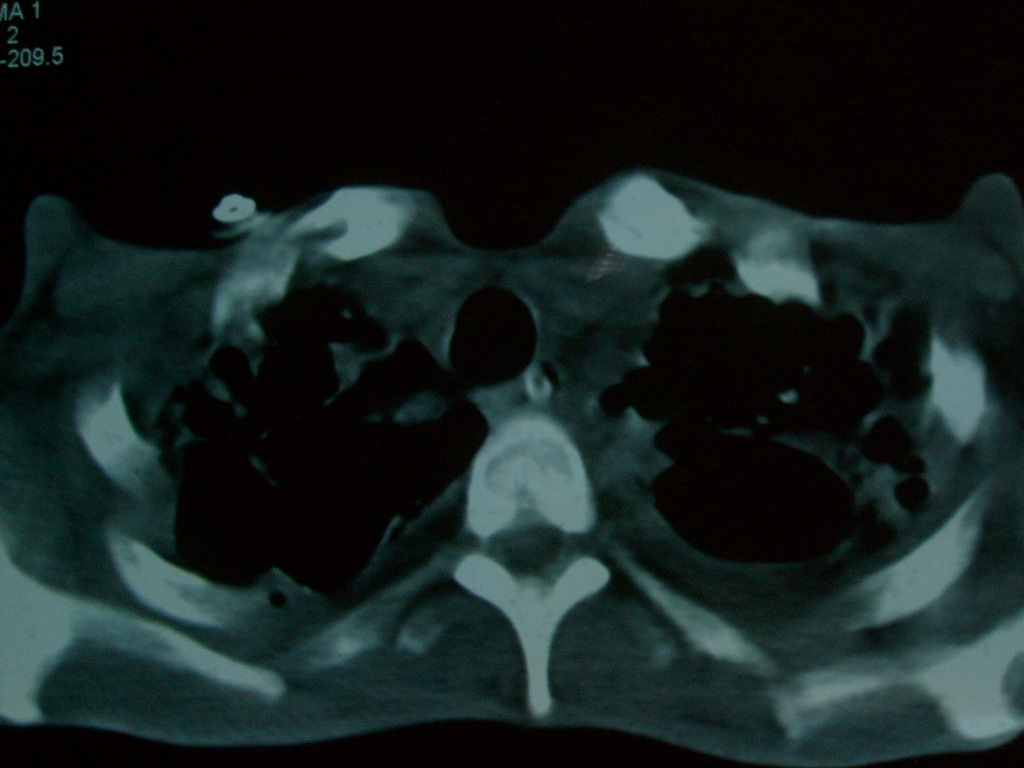

标题: CT10510:男.18岁,咳嗽咳痰两月.(有病理) [打印本页]

标题: CT10510:男.18岁,咳嗽咳痰两月.(有病理)

双肺布满大片状实变及网格状结节影,内参杂大小不等的气囊及空气支气管征,双侧胸膜腔少量积液,双下肺近膈面透亮度尚可,病人较年轻,病变较重(不知为什么上胃管?)考虑:1.胶原病肺部改变,2.组织细胞病x。结合实验室检查。

首先考虑组织细胞x病。两肺中上肺野多发囊腔,中下肺野内见多发小结节,并可见肺间质增厚。患者是男性,年龄较小。胶原性病变比较多见的类风湿、系统性红斑狼疮和硬皮病临床和影像均不是很支持,类风湿和系统性红斑狼疮的肺部表现最常见的是胸腔积液,硬皮病可见食管的扩张。

双肺结核并播散.患者以肠梗阻入院,手术为肠结核.术后咳嗽做ct检查.